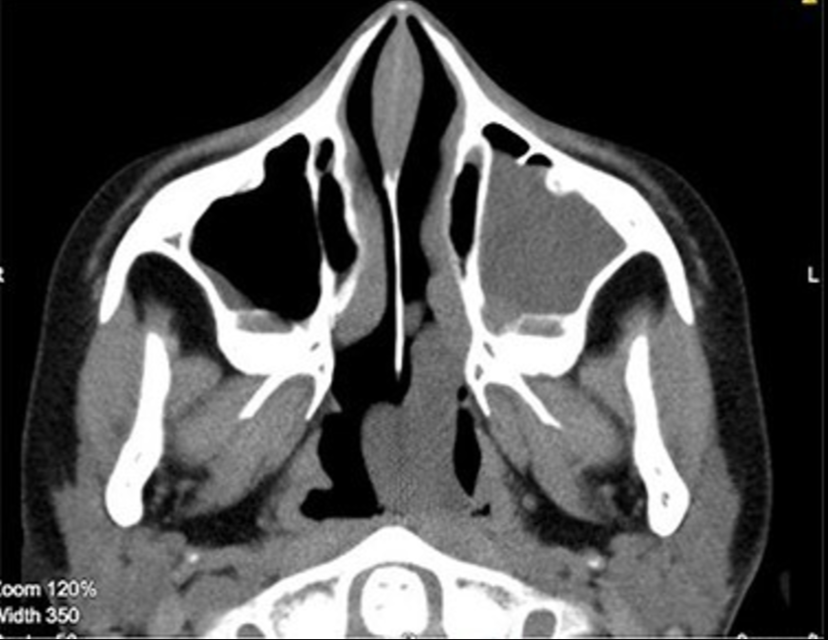

前鼻镜检查显示下鼻甲肥大,粘膜过敏,分泌物增多,未见新生物。鼻内无持续性脓性鼻漏。在咽喉检查中,见一个巨大的红色草莓状肿物在口咽部向后脱垂。对左鼻孔进行了鼻内窥镜检查 (FNE),显示从中鼻道延伸到后鼻孔的息肉和清晰的右气道。进行了计算机断层扫描 (CT) 扫描(图1和图2)显示从左中鼻道产生的软组织肿物,向后延伸并到达左侧后鼻孔(图 2)。

图2

鼻内镜检查和 CT 扫描放射学评估是诊断 ACP 的金标准。鼻内窥镜检查显示 ACP 为从中鼻道出现的平滑息肉状肿块,延伸至后鼻孔和鼻咽。CT 扫描的主要发现是软组织肿块,不会侵蚀相邻的骨结构。CT 扫描也用于 ACP 的分期分类。磁共振成像可用于辅助诊断并排除血管瘤性息肉。